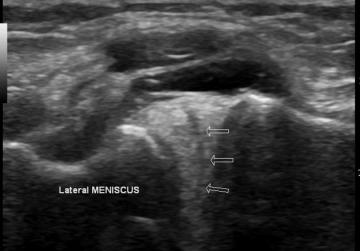

Ultrasonografia to jedyne, tak szybkie i wiarygodne badanie z szeregu dostępnych możliwości obrazowania narządu ruchu. W kilka chwil pozwala na ocenę uszkodzeń stawowych, dla przykładu zdjęcie uszkodzonej łąkotki bocznej (łac. meniscus lateralis).